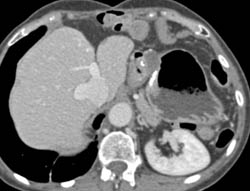

Gastric Cancer